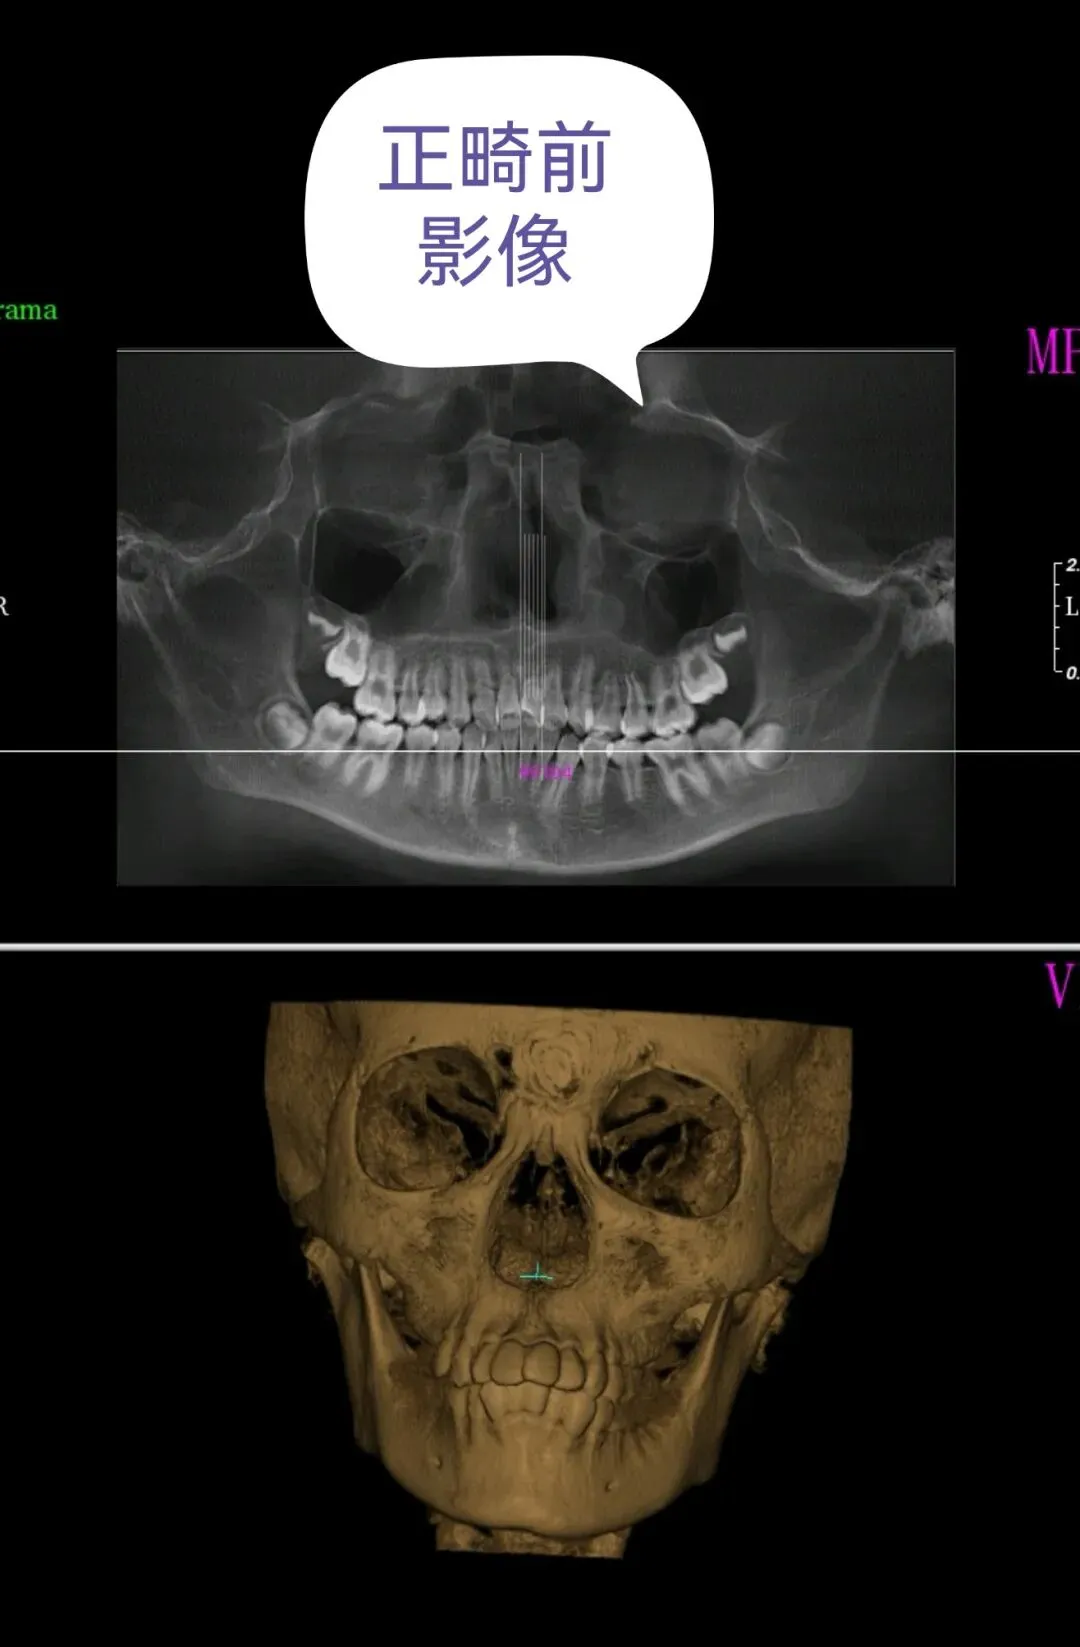

孩子10岁那年,因牙齿不齐,我们本着对公立三甲医院的信任,特意选择了专业对口的南昌大学附属口腔医院进行正畸。

孩子正畸前拍片是没有囊肿的,矫正途中出现的。